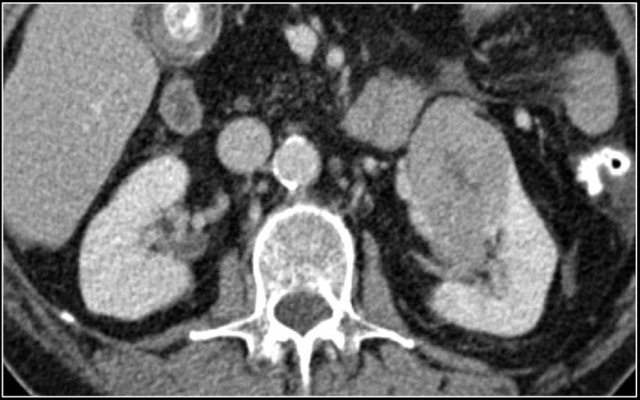

The kidney is a common extranodal site of lymphoma involvement, especially in Non-Hodgkin lymphoma.

Primary involvement of the kidney is rare.

Renal lymphoma usually presents as multiple poorly enhancing masses, but may also present as retroperitoneal tumors directly invading the kidneys or as perirenal soft-tissue masses.

Diffuse infiltration of the renal interstitium results in nephromegaly and is more common in Burkitt lymphoma.

The image shows bilateral involvement of the kidney and a bone lesion in a patient with B-cell lymphoma.

Here another patient with lymphoma located in the mediastinum, pancreas (arrow) and in both kidneys.

Diffuse enlargement of both kidneys in a patient with lymphoma.